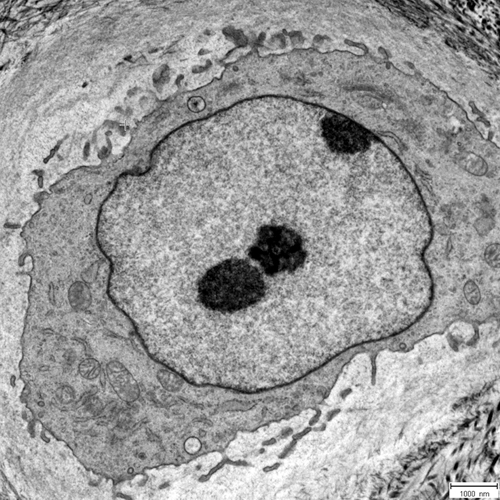

Traumatised IVDs of the cervical spine are studied histologically by means of light microscopy and ultrastructurally by means of transmission electron microscopy (TEM). The group is conducting investigations on the basis of two parameters: fracture mechanism (compression vs. rotation fractures) and degeneration grade (low vs. high). Disc architecture is studied histologically; cell morphology is examined ultrastructurally, in order to quantify cell death, healthy cells and balloon cells. Based on ultrastructural observations, two time groups (up to 6 days / longer) are being investigated. Degenerative disc diseases presented a new disc cell morphology, the balloon cell, which we first detected by means of transmission electron microscopy. The aim is to examine this special cell morphology in detail. These cells also seem to be a part of aging processes in the IVD, cartilage and adjacent bone structures. Furthermore, the group is studying intervertebral disc cells in the degenerated cervical spine with prolapse or protrusion and in the cervical spine post-trauma in cell culture, to analyse cell morphology as well as pro-inflammatory and pro-apoptotic proteins with special regard to balloon cells. Whereas these cells were obvious at a mean of 40% in the disc matrix, the cell culture presented up to 98% balloon cells. This may have an influence in an upcoming therapy.